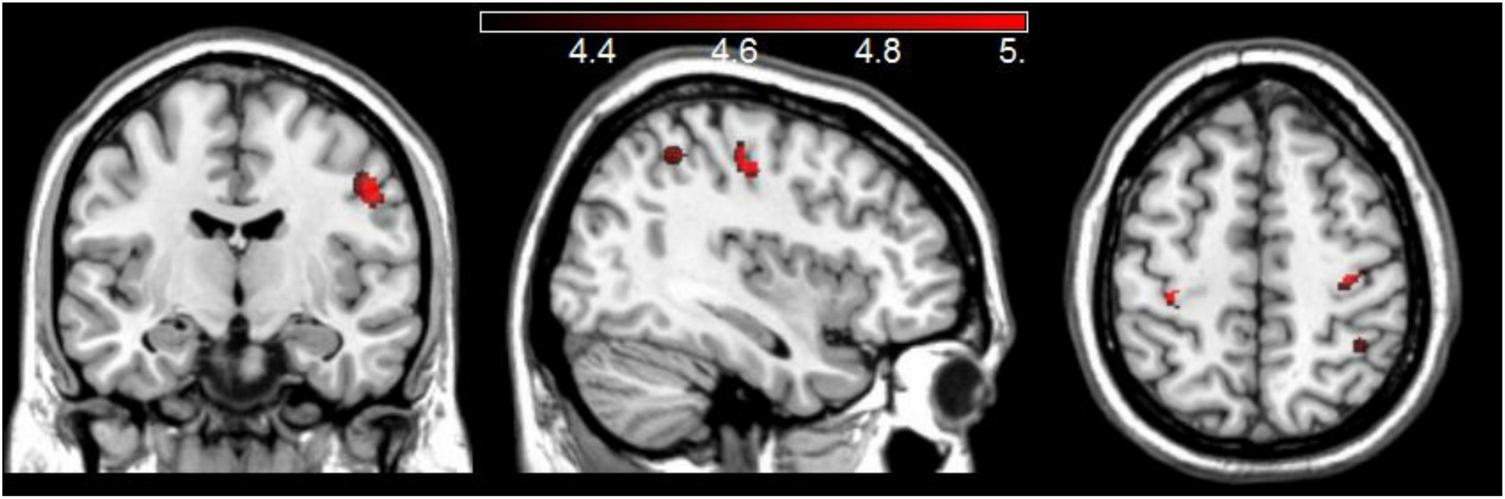

The whole-brain analysis of groups’ GM maps with proverbs scores as covariate of interest, and sex and TIV as covariates of no interest, revealed clusters with significantly more GM volume in YA than in OA in the right middle-frontal gyrus and in the precentral and postcentral gyri bilaterally. These clusters survived a correction for multiple comparisons at FWE p < 0.05 (Figure 2).

FIGURE 2

Areas with more GM in YA compared to OA when considering the groups’ proverbs scores and adjusting for sex and TIV.

Consistent with previous findings on age-related brain atrophy, older participants in our study had significantly reduced GM volumes relative to YA. However, an unexpected finding based on comparisons of voxel-based morphometry measurements between OA and YA links more GM volume in the right middle-temporal gyrus, and pre- and post-central gyri bilaterally, with lower proverbs scores. The direction of this relationship is surprising, because greater GM volumes in frontal and temporal areas are typically associated with better performance on tests of crystalized abilities, such as retrieval of information from stored knowledge (Hoffman et al., 2017). Nevertheless, some studies reported the opposite pattern. For instance, de Zubicaray et al. (2011) found that better semantic ability in cognitively healthy older adults was associated with reduced GM volumes in a predominantly left-hemisphere network, which included the middle temporal gyrus. A recent study comparing brain activation patterns during interpretation of familiar and unfamiliar proverbs reported that unfamiliar proverbs activated the middle-temporal gyrus bilaterally, among other areas (Bohrn et al., 2012). The authors explained the activation of this area in interpretation of unfamiliar proverbs in terms of neural support in semantic integration and sentence processing, which is consistent with the finding on association of this area with lower accuracy in the interpretation of proverbs in YA in our sample.